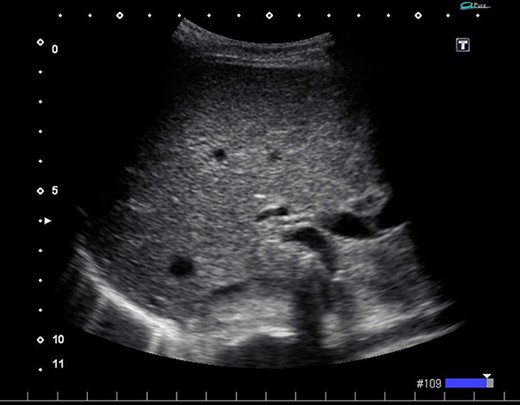

On admission, her vital signs were normal. Her medical history included dermatomyositis, hypertension and osteoporosis. She had a white blood cell count of 10.6 × 103/μL, hemoglobin of 8.2 g/dL and lactic acid of 0.8 mmoL/L. A physical examination demonstrated strong tenderness in her right upper quadrant abdomen. Ultrasonogramphy (US) showed diffuse wall thickening of her gallbladder without cholecystolithiasis. US also revealed small mobile echogenic foci moving inside the portal venous branches (Fig. 1). The hyperechogenic foci were seen in the middle segment and right anterior segment of the liver. Contrast-enhanced computed tomography (CT) showed a diffusely thickened wall of the gallbladder with poor enhancement, suggesting acute necrotizing cholecystitis (Fig. 2). Tiny bubbles were seen in the intrahepatic portal venous branches (segment 4 and segment 5), but there was no evidence of bowel ischemia. She was then diagnosed with necrotic cholecystitis and immediately underwent emergency operation.

(A) Ultrasonography shows distention and wall thickening of the gallbladder. (B) Ultrasonography shows small mobile echogenic foci and hyperechogenic linear structures in the middle segment and right anterior segment of the liver.